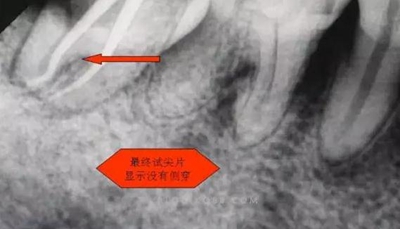

1.拍片基本可以確定遠(yuǎn)中頰側(cè)根管是一個(gè)融合根管,也就是常見(jiàn)的C型根管,粗大的根管口是扁形,根管同樣呈扇貝型,根尖孔粗大。而且在根管中上段較粗大,插針拍片后遠(yuǎn)中顯示根管有側(cè)穿的可能,但是通過(guò)內(nèi)窺鏡顯示是沒(méi)有任何側(cè)穿點(diǎn),也沒(méi)有滲血和患者有疼痛現(xiàn)象。這個(gè)病例告訴我們,有時(shí)候做根管治療,為了把根管做通和預(yù)備到位,必要的牙體組織去除是可以的,后期可以用冠修復(fù)來(lái)彌補(bǔ),如果不去除,本病例的根管治療,根充時(shí)可能會(huì)面臨充填不嚴(yán)密,從而導(dǎo)致根管治療的失敗,這是不可取的。

6.本病例,由于連接近遠(yuǎn)中2個(gè)根管的融合區(qū)頰舌徑過(guò)于狹窄,在x線片上顯示不清,而唯一能表現(xiàn)的是近遠(yuǎn)中分離的2個(gè)獨(dú)立的根管,將K銼放置到頰側(cè)根管內(nèi),有時(shí)在x線片上表現(xiàn)出根分叉處可能穿孔,這也是C型根管在x線上的重要特征。